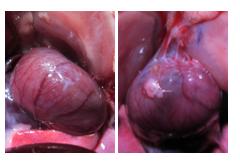

A hydrogel that forms a barrier to keep heart tissue from adhering to surrounding tissue after surgery was developed and successfully tested in rodents by a team of University of California San Diego researchers. The team of engineers, scientists and physicians also conducted a pilot study on porcine hearts, with promising results.

In rats, the hydrogel prevented the formation of adhesions altogether. In a small pilot study, porcine hearts treated with the hydrogel experienced less severe adhesions that were easier to remove. In addition, the hydrogel did not appear to cause chronic inflammation.

In academic medical centers such as UC San Diego, most surgeons conduct repeat operations and encounter adhesions fairly regularly. In this study, in rats, 70 percent of animals in the control group developed severe adhesions.